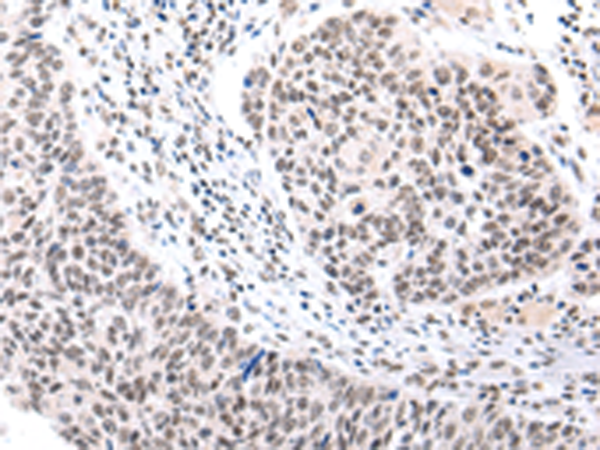

分类: 科研抗体货号: P12470别名: MRP; ABCC; GS-X; MRP1; ABC29应用: WB,IHC反应种属: Human